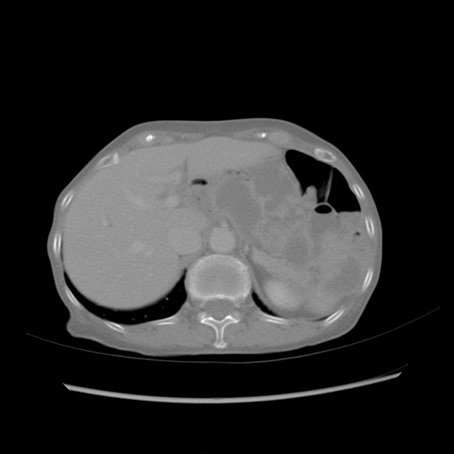

冠状断像

【症例】80歳代女性

【主訴】胸のつかえ感

【現病歴】約9時間前に食後から胸のつかえた感じあり、嘔吐あり、来院。

【既往歴】胃癌(全摘)、胆摘、虫垂炎

【身体所見】心窩部に圧痛あり、反跳痛なし。

【データ】WBC 5700、CRP 0.05